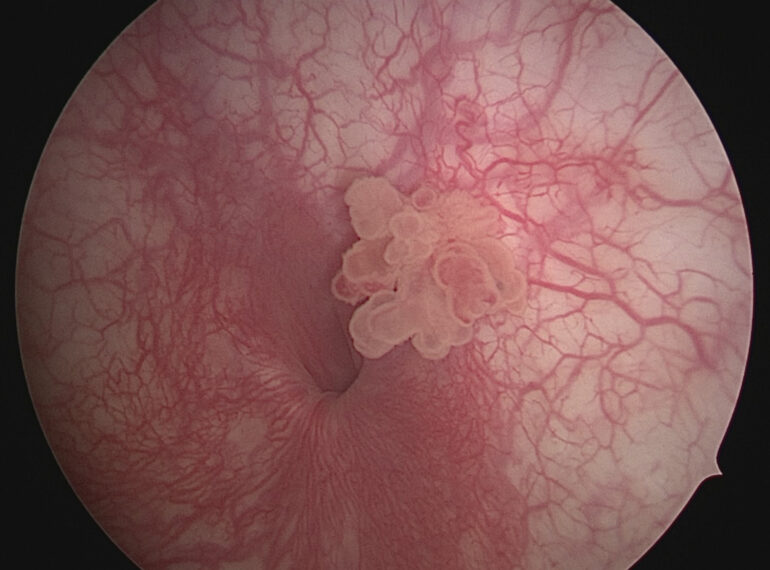

HPV